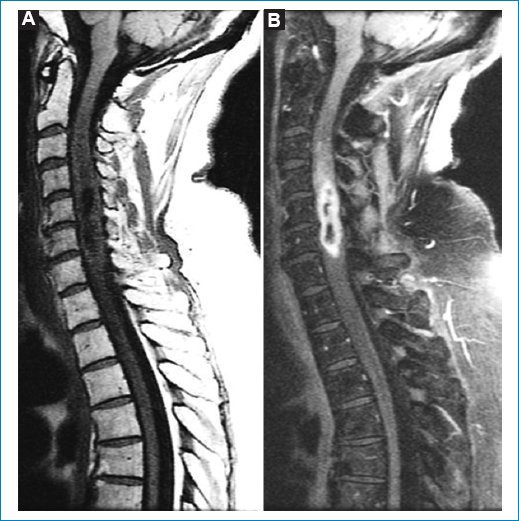

Resonancia magnética

Se aprecia un tumor intradural intramedular que tiene una extensión de cuatro vértebras, desde C3 a C6 (Figs. 14).

Figura 3. Secuencia STIR. (A) Corte central. (B) Corte contiguo. (C) Ampliación de A. Hiperintensidad extensa y homogénea de la médula espinal afectada que excede el volumen tumoral sólido que se verá en la secuencia ponderada en T1.

Figura 4. (A) Secuencia sagital ponderada para T1 sin contraste. (B) Secuencia sagital STIR después de administrar contraste paframagnético. Tras la administración de gadolinio en secuencia STIR se observa realce periférico en anillo (rim enhancement).

Tiene una posición central con una porción quística intratumoral. La lesión es isointensa en T1 e hiperintensa en T2 y STIR (Figs. 15). Después de administrar contraste paramagnético endovenoso hay realce periférico, especialmente alrededor de la formación quística. Por debajo del polo inferior se ve siringohidromielia de corto trayecto. Las características de las imágenes coinciden con las descripciones que aparecen en la bibliografía35.